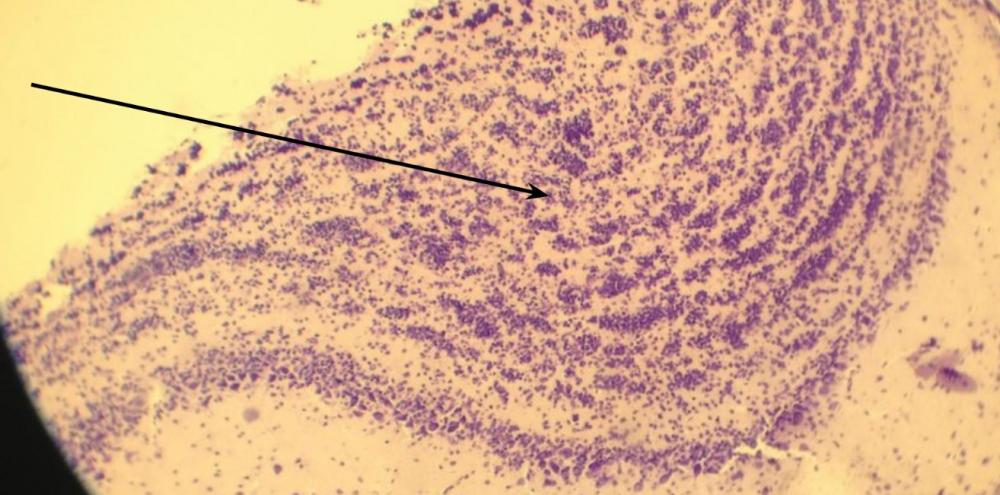

Pytanie 170

róg Amona, zbudowany z komórek piramidalnych (cytoarchitektura kory mózgu, barwienie fioletem krezylu Nissla)

Pytanie 171

zakręt zębaty, zbudowany z komórek ziarnistych (cytoarchitektura kory mózgu, barwienie fioletem krezylu Nissla)